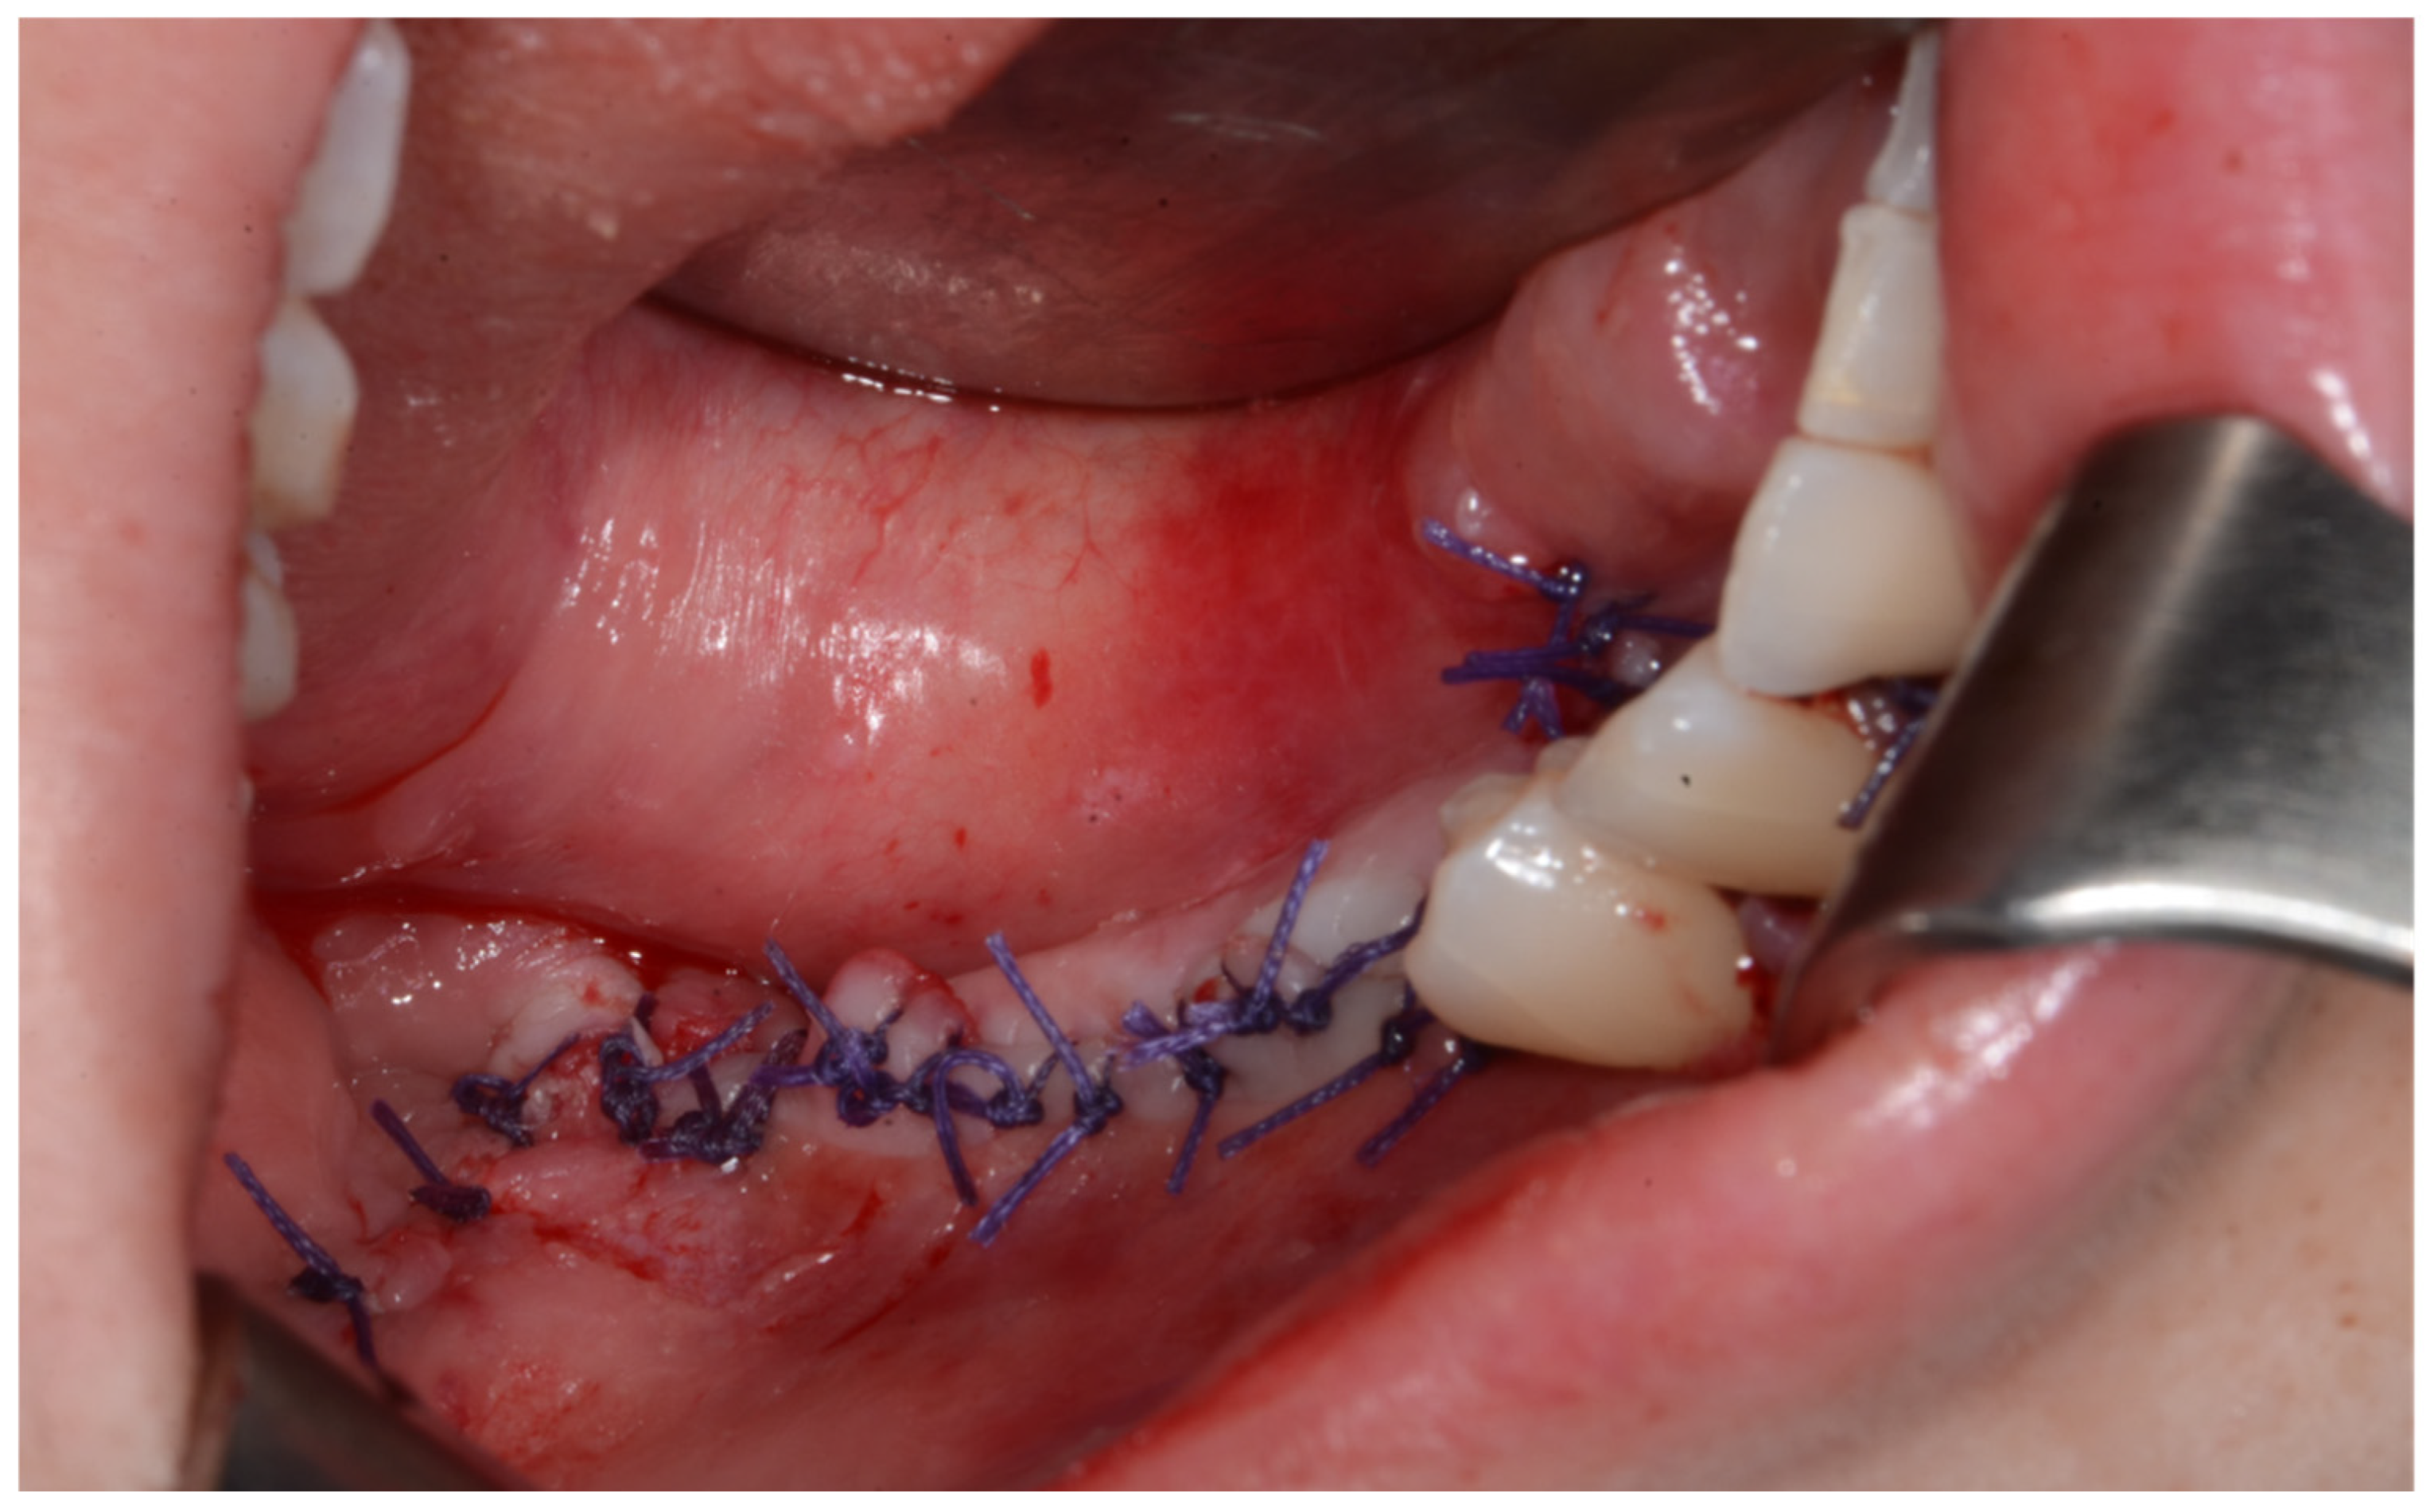

Surgery was performed under general anesthesia. #45, 46, and 47 were extracted. Segmental mandibulectomy was performed using a surgical guide through a submandibular approach. (Figure 6). The left iliac crestal DCIA flap was harvested according to the surgical guide. (Figure 7) To minimize the morbidity of the donor site, the donor site was reconstructed using titanium mesh and allobone chip graft. (Figure 8) Microvascular anastomosis was performed using the facial artery and facial vein. Fixation of the resected mandible and the bicortical iliac bone flap was achieved using a customized reconstruction plate (Cusmedi ©, Sungnam, Republic of Korea) designed to have a thickness of 2 to 3 mm according to the patient’s mandibular morphology and the periphery of the iliac bone flap and 3D printed by the selective laser melting (SLM) method and eight 2.3 mm reconstruction screws. (Figure 9). A silastic drain was inserted into the submandibular region and sutured. (Figure 10) The final diagnosis was ameloblastoma.

Figure 10.

After primary closure.